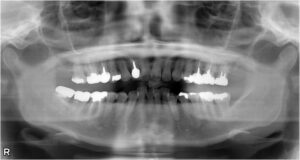

• 上下臼歯5本欠損症例

BEFORE AFTER 74歳女性/上下5本欠損/インプラント埋込手術 【治療内容】 右上第二小臼歯、第一、第二大臼歯…